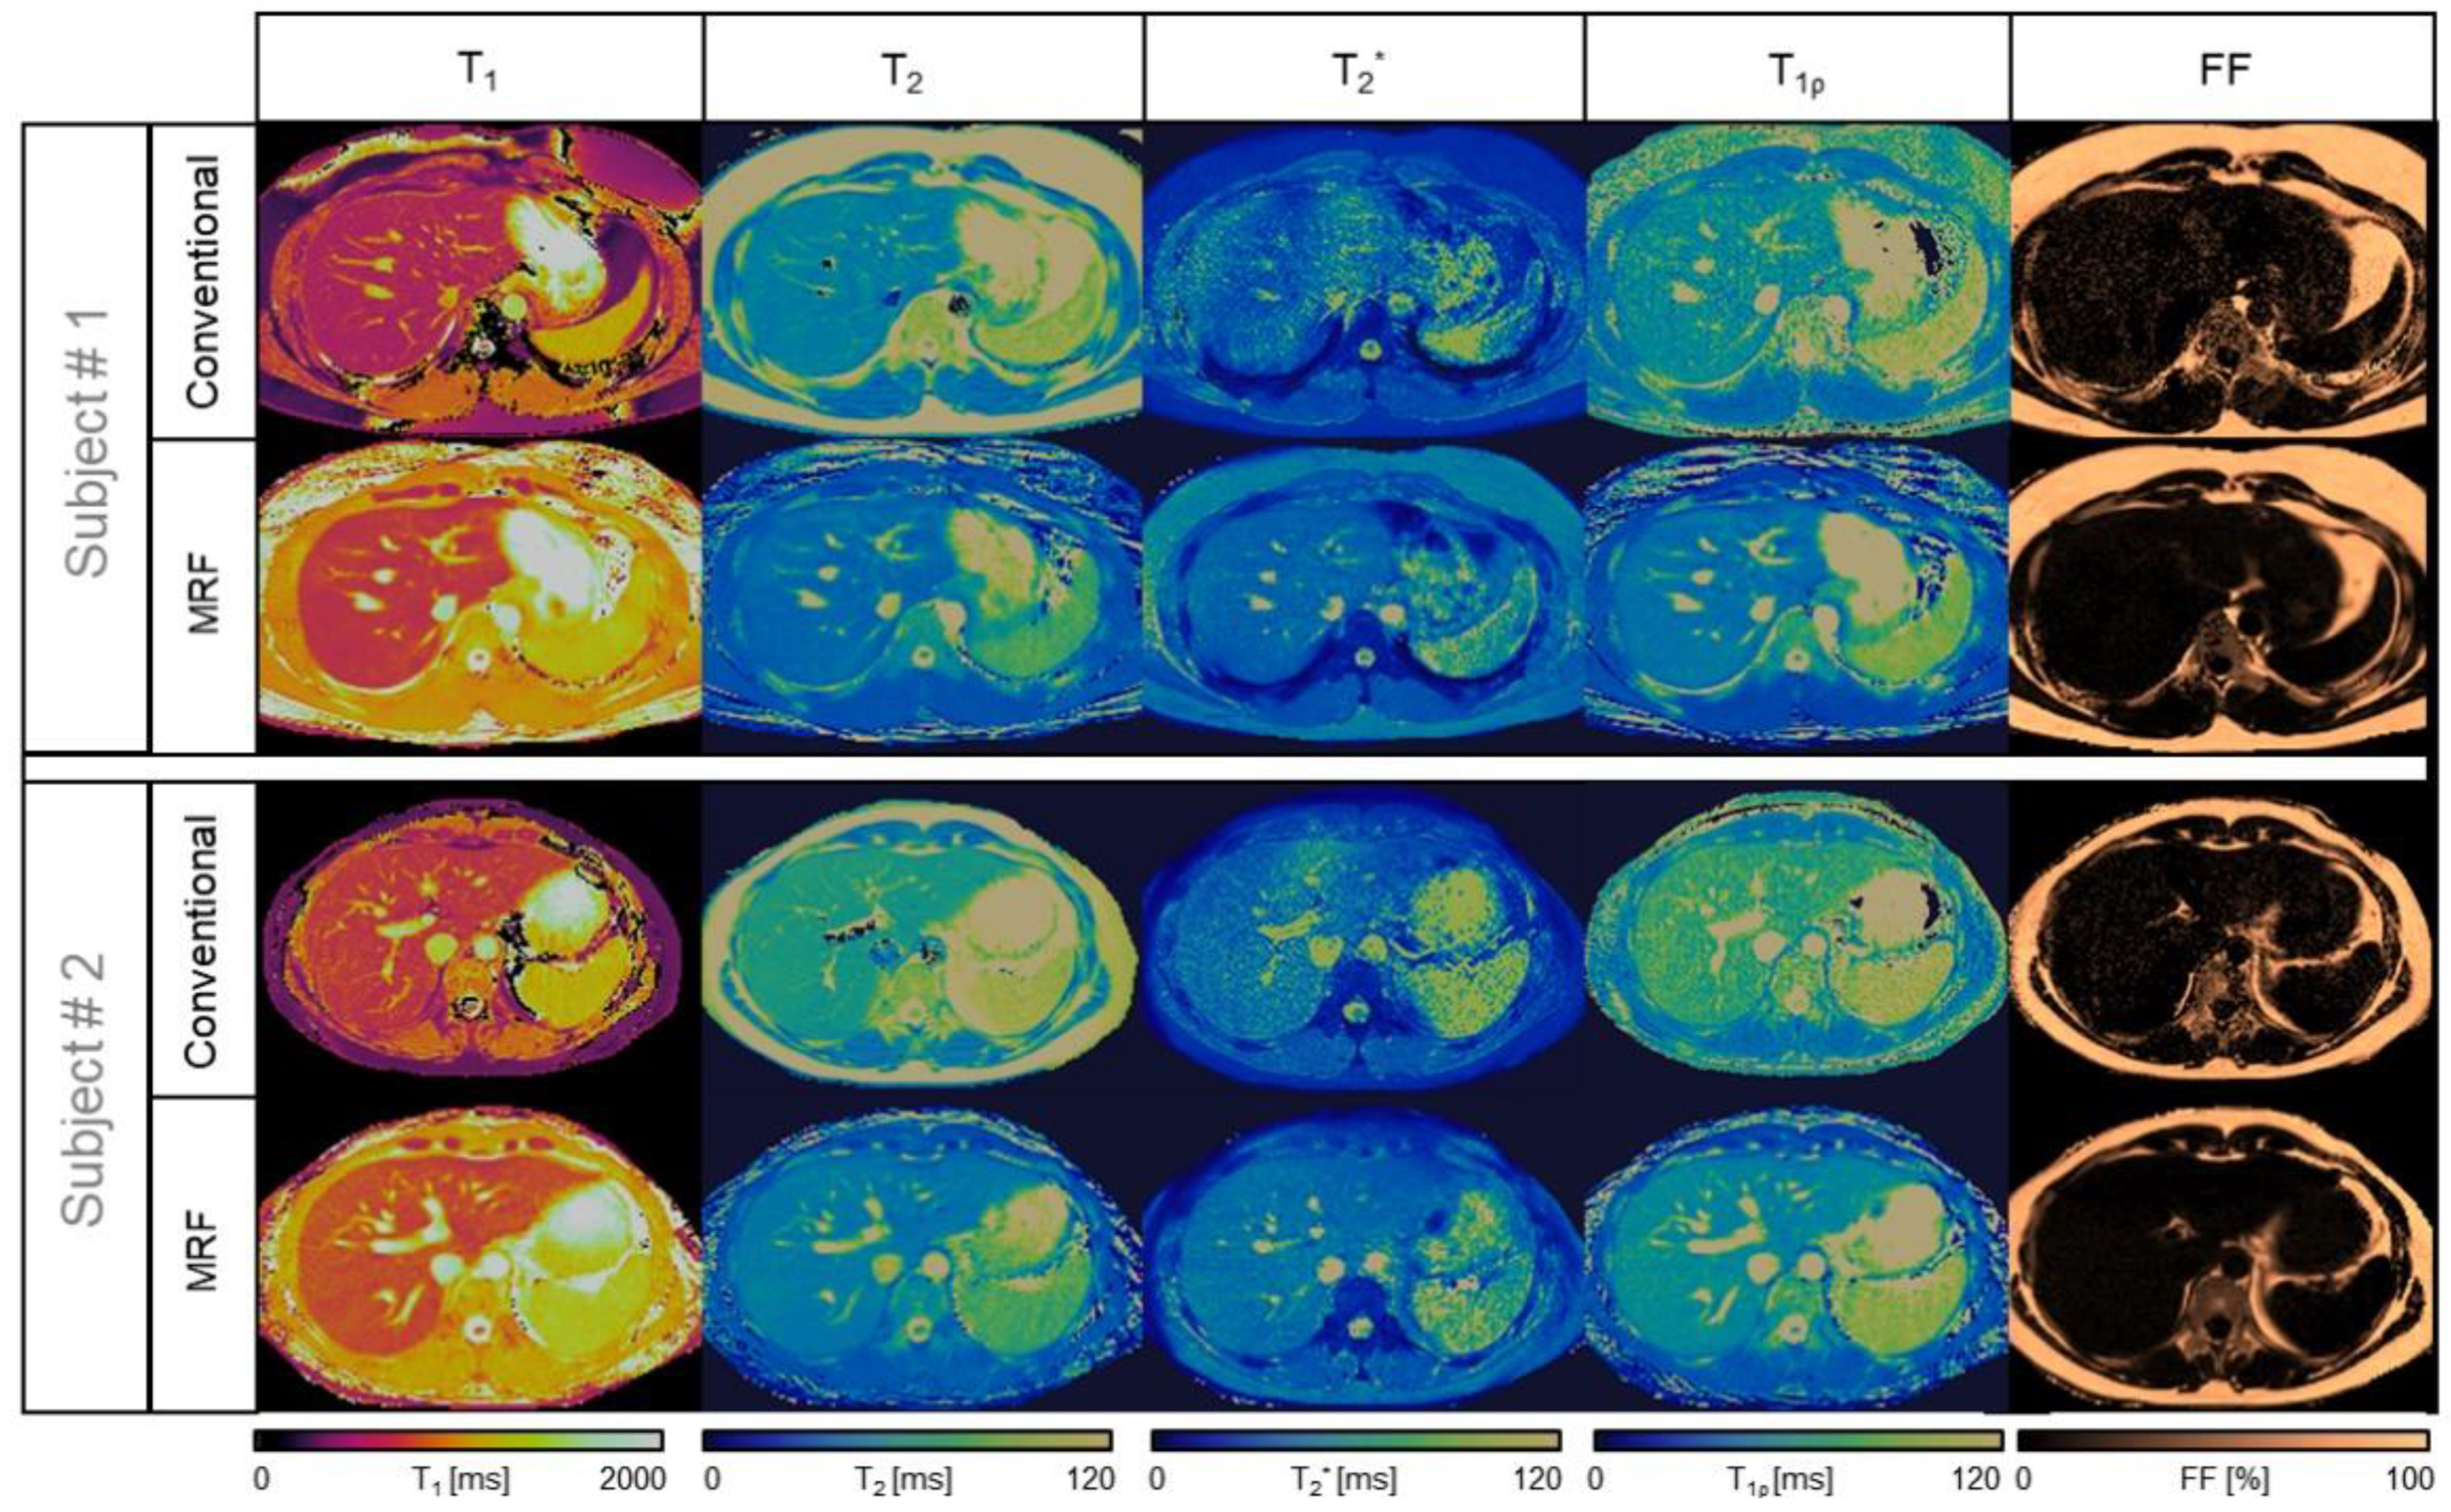

Figure 1.

Comparison between liver MRF maps and conventional images from two healthy subjects. The conventional referencing sequences are (top row, left to right for each subject) T1-MOLLI, T2-GraSE, 8-echo GRE T2 *, T1⍴-TFE, and 6-echo GRE FF, compared against the proposed inherently co-registered T1, T2, T2 *, T1ρ, and FF abdominal MRF maps (bottom row left to right for each subject) obtained from a single 18 s scan.